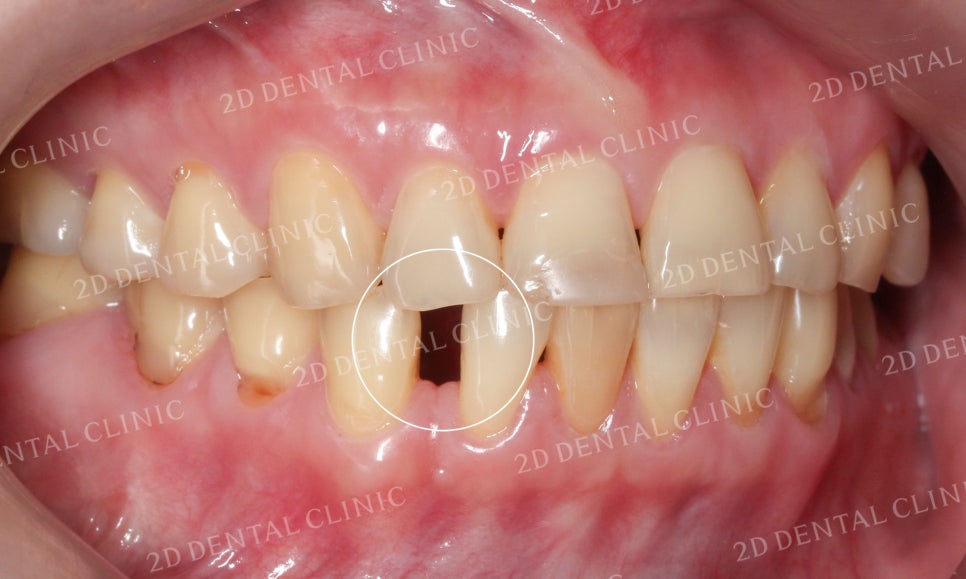

특히 치간이개가 심했던 우측의 안모 사진입니다.

하악의 상태가 심각했는데

블링스 시술 후 빈 공간이

어디었는지 찾을 수 없을만큼

완벽하게 수복된 모습이네요!